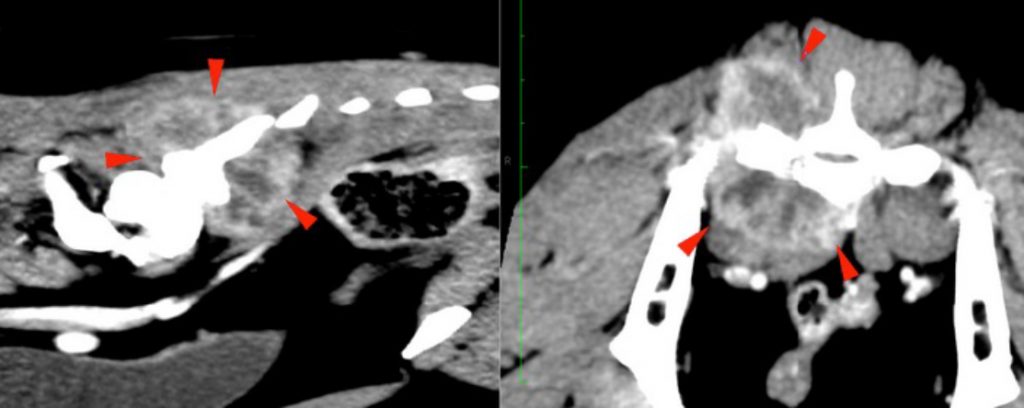

There is a well-defined, irregular to ovoid mass centred at the right caudal aspect of the sacrum (red arrowheads). It is soft tissue attenuating with mineral attenuating foci medially and showing heterogeneous strong contrast enhancement with hypoattenuating and poorly enhancing areas within. It is causing the moth-eaten lysis of the right body of the sacrum (green arrowheads) with irregular margination of the right ventral sacral foramina (blue arrowheads). There is a periosteal reaction noted dorsal to the right sacroiliac joint and ventral caudal sacral body. The mass is invading the sacral canal to this level with complete attenuation of the perineural fat at the level of the right ventral sacral foramina.

The right medial iliac lymph nodes are prominent compared to the left, preserving normal shape and measuring 9 mm in width. They show normal attenuation and contrast enhancement.